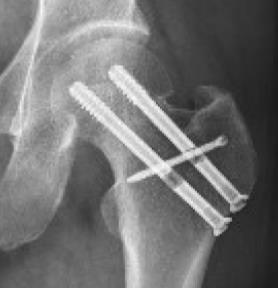

SimpliFix Hip System

• The SimpliFix Hip System is a percutaneous fixation construct for minimally displaced or non-displaced intracapsular femoral neck fractures, designed to mitigate complications seen with parallel screw constructs or dynamic hip screw alone. The system pairs two large-diameter cannulated screws with a targeted headless cross screw that keys through a slot in the superior screw to add rotational control. Using a dedicated targeting arm, the surgeon selects 0 mm (no dynamization) or 3 mm (controlled settling) of compression to help resist femoral neck shortening while maintaining native neck length and femoral offset.

• The cross-screw technique enhances rotational stability and helps prevent lateral head migration, supporting alignment and reducing the risk of additional shortening. Preserving femoral neck length correlates with improved pain and function in postoperative recovery, making controlled compression and rotational control clinically meaningful endpoints.

• SimpliFix trajectories place an inferior calcar screw for axial support and a central–superior screw oriented toward the anterior–superior head, preserving bone stock while providing a dedicated slot for the cross screw.

• These vectors resist varus collapse and shortening.

• Drive and seat the inferior SimpliFix cannulated screw (Ø 8.3 mm, 16 mm thread, blunt, self-tapping head).

• Assemble the SimpliFix T-handle and retaining bolt; secure the superior SimpliFix screw (ensure fins engage the mating slots).

• Insert the headless cross screw (Ø 3.7 mm) with a T8 driver; power to near seat, then hand-seat to cortex.

• Final verification: anteroposterior and lateral fluoroscopy to confirm reduction, implant positions, and cross-screw engagement with the superior screw slot.